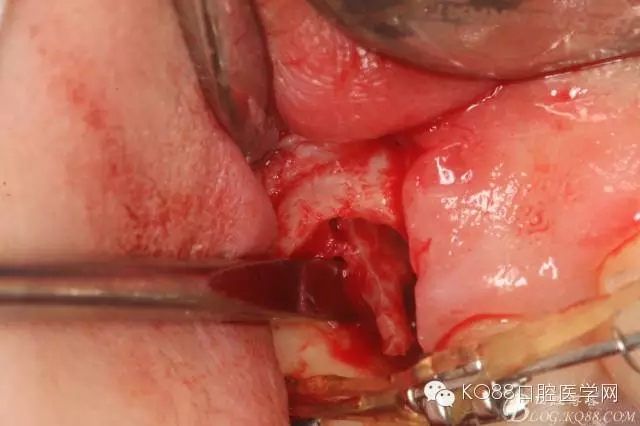

圖11.仔細(xì)考慮之后,在14頰側(cè)做垂直切口,切口長度僅達(dá)膜齦聯(lián)合處,做小切口。

圖12. 做垂直切口+齦溝內(nèi)切口,形成角形瓣,暴露出15根面。